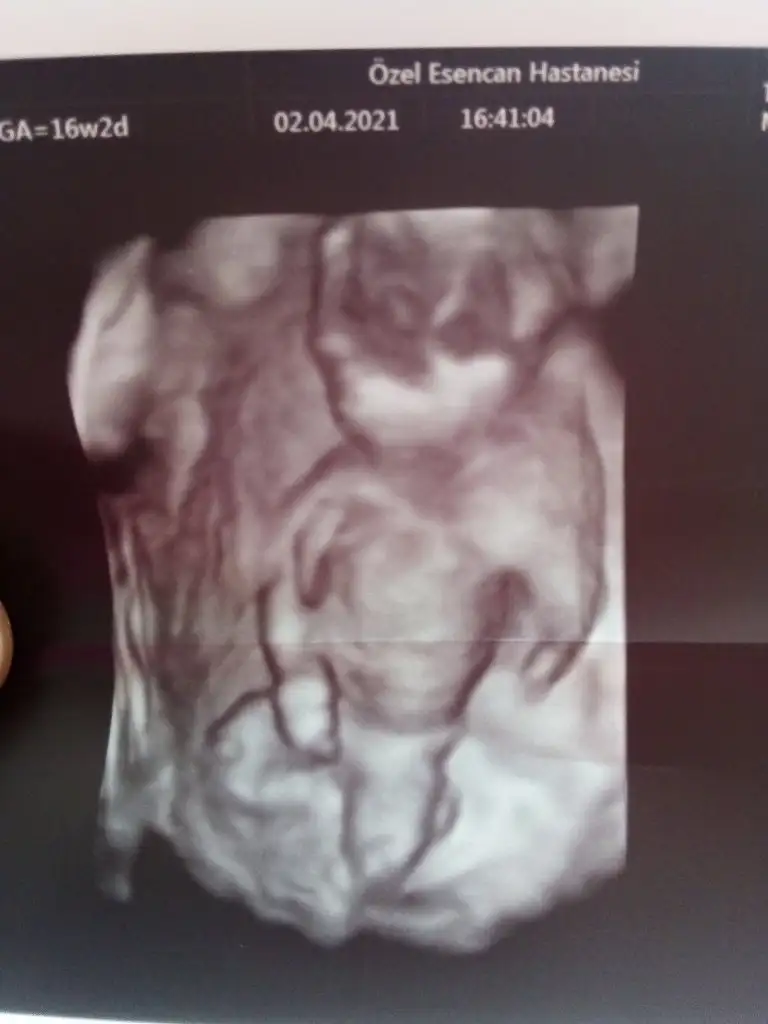

Bizede bakarmisiniz 12 haftalik oldukBizede bakar mısınız 10 haftalığız

Bizede bakarmisiniz lütfeennnBence ikiside kiz doktor ne dedi ilki icin?